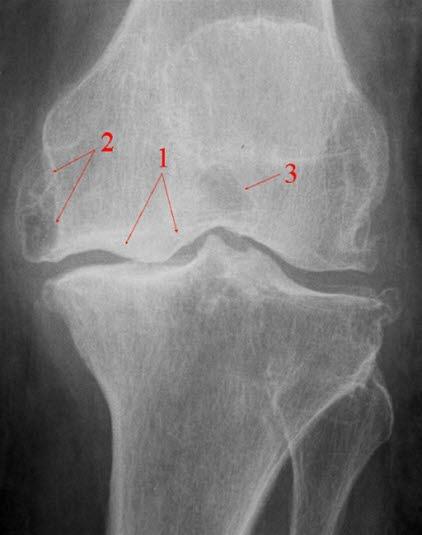

Røntgenbilde av kneleddetKneleddet utgjøres av lårbeinets og leggbeinets leddflater. Beinvevet er kledd med brusk som gjør at leddflatene glir mot hverandre med minst mulig motstand. I tillegg har kneleddet to bruskskiver (meniskene) som fremmer bevegeligheten i leddet. Artrose i kneleddet kalles det når leddbrusk eller bein i kneleddet er endret slik at overflatene ikke lenger er glatte og symmetriske. Dette kaltes tidligere slitasjegikt.

Røntgen av kneet viser typiske artroseforandringer (lette, moderate, uttalte artroseforandringer) og bekrefter diagnosen. Røntgenbildene forteller likevel ikke hele sannheten, fordi det kan være manglende samsvar mellom graden av plager og graden av forandringer på røntgen.